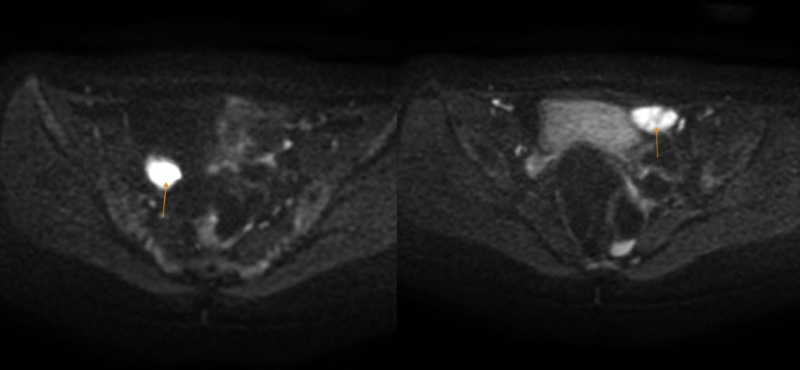

Thay vào đó, tại vùng hạ vị xuất hiện các khối tổ chức nghi ngờ là tinh hoàn lạc chỗ. Đây là dấu hiệu gợi ý đến một rối loạn phát triển giới tính hiếm gặp.

Hình ảnh các khối tổ chức tại vùng hạ vị, nghĩ nhiều tới tinh hoàn lạc chỗ